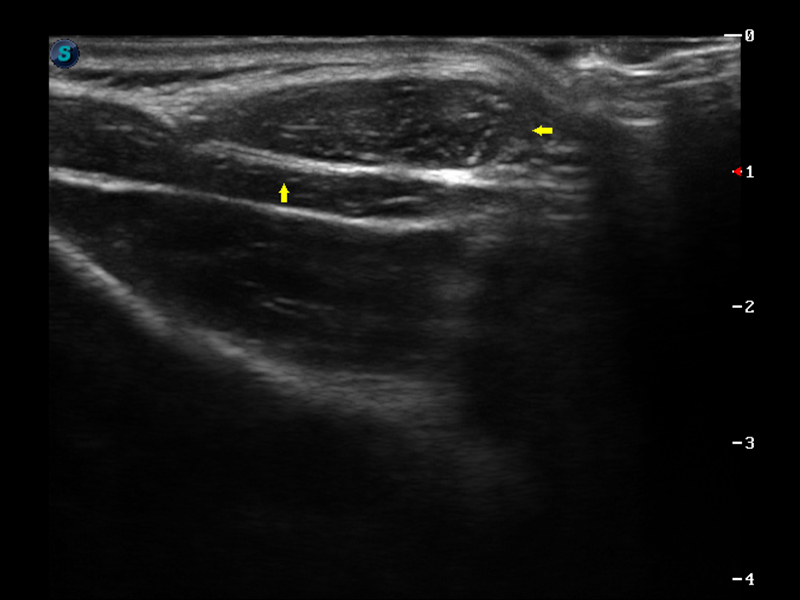

S9便携式彩色多普勒超声诊断仪是狗万官方网站研发的高端便携彩超设备,外观设计新颖、产品性能卓越。S9在便携超声领域采用了突破传统的触摸屏交互设计,并以先进的软件硬件技术和设计理念,为您带来清晰的图像质量、稳定的工作性能和便捷的操作体验。

弹性成像